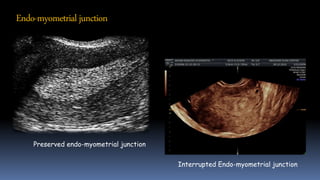

• Endo-myometrial interface - Junctional zone

Interrupted Endo-myometrial junction

Preserved endo-myometrial junction

Endo-myometrial junction

Interrupted Endo-myometrial junction Preservedendo-myometrial junction Endo-myometrial junction